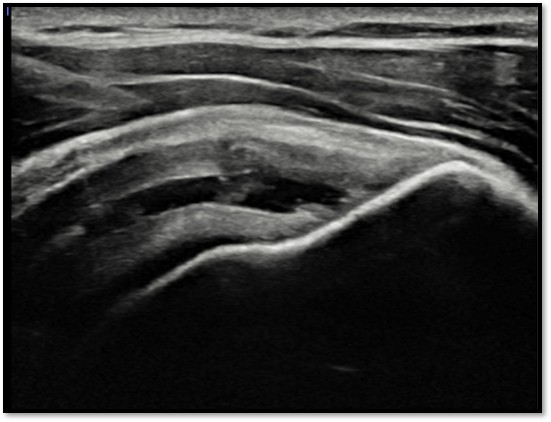

케이스 1: 관절면측 파열 → 축소봉합술

환자: 45세 남성, 테니스 동호회

진단:

MRI: 극상건 관절면측 부분파열 (약 40%)

파열 양상: 가로 파열, 깔끔함

치료:

축소봉합술 (특수 드릴 + 콜라겐 봉합사)

재생주사 병행

재활 운동

결과:

12주 후 초음파: 봉합 부위 안정적 유지

6개월 후 테니스 복귀